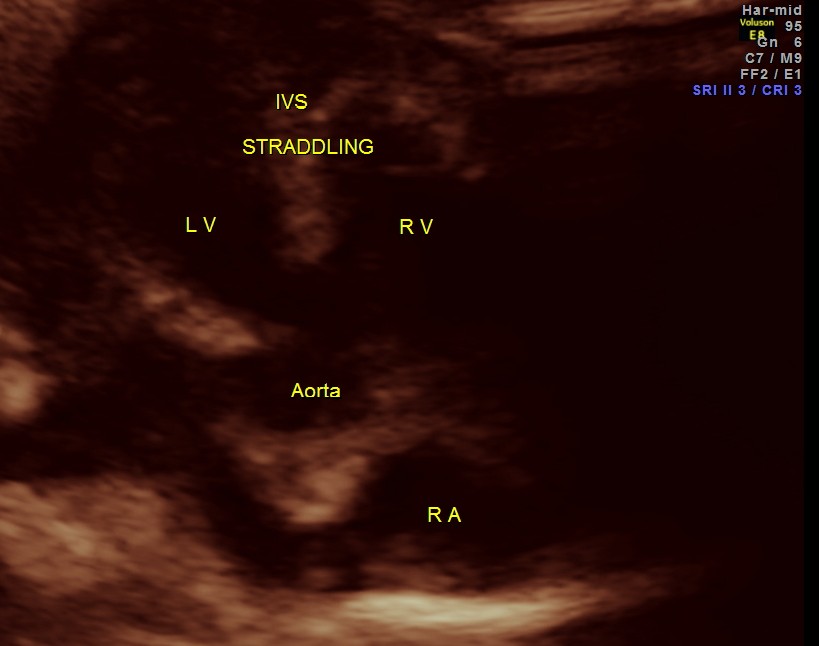

The following pictures are of the heart of the child .

The IVS straddling the aorta is prominently seen ; The RV is mildly dilated . Though the pulmonary artery was difficult to comment on , I would still go with TETRALOGY OF FALLOT with RENAL DYSPLASIA , which makes it complicated.